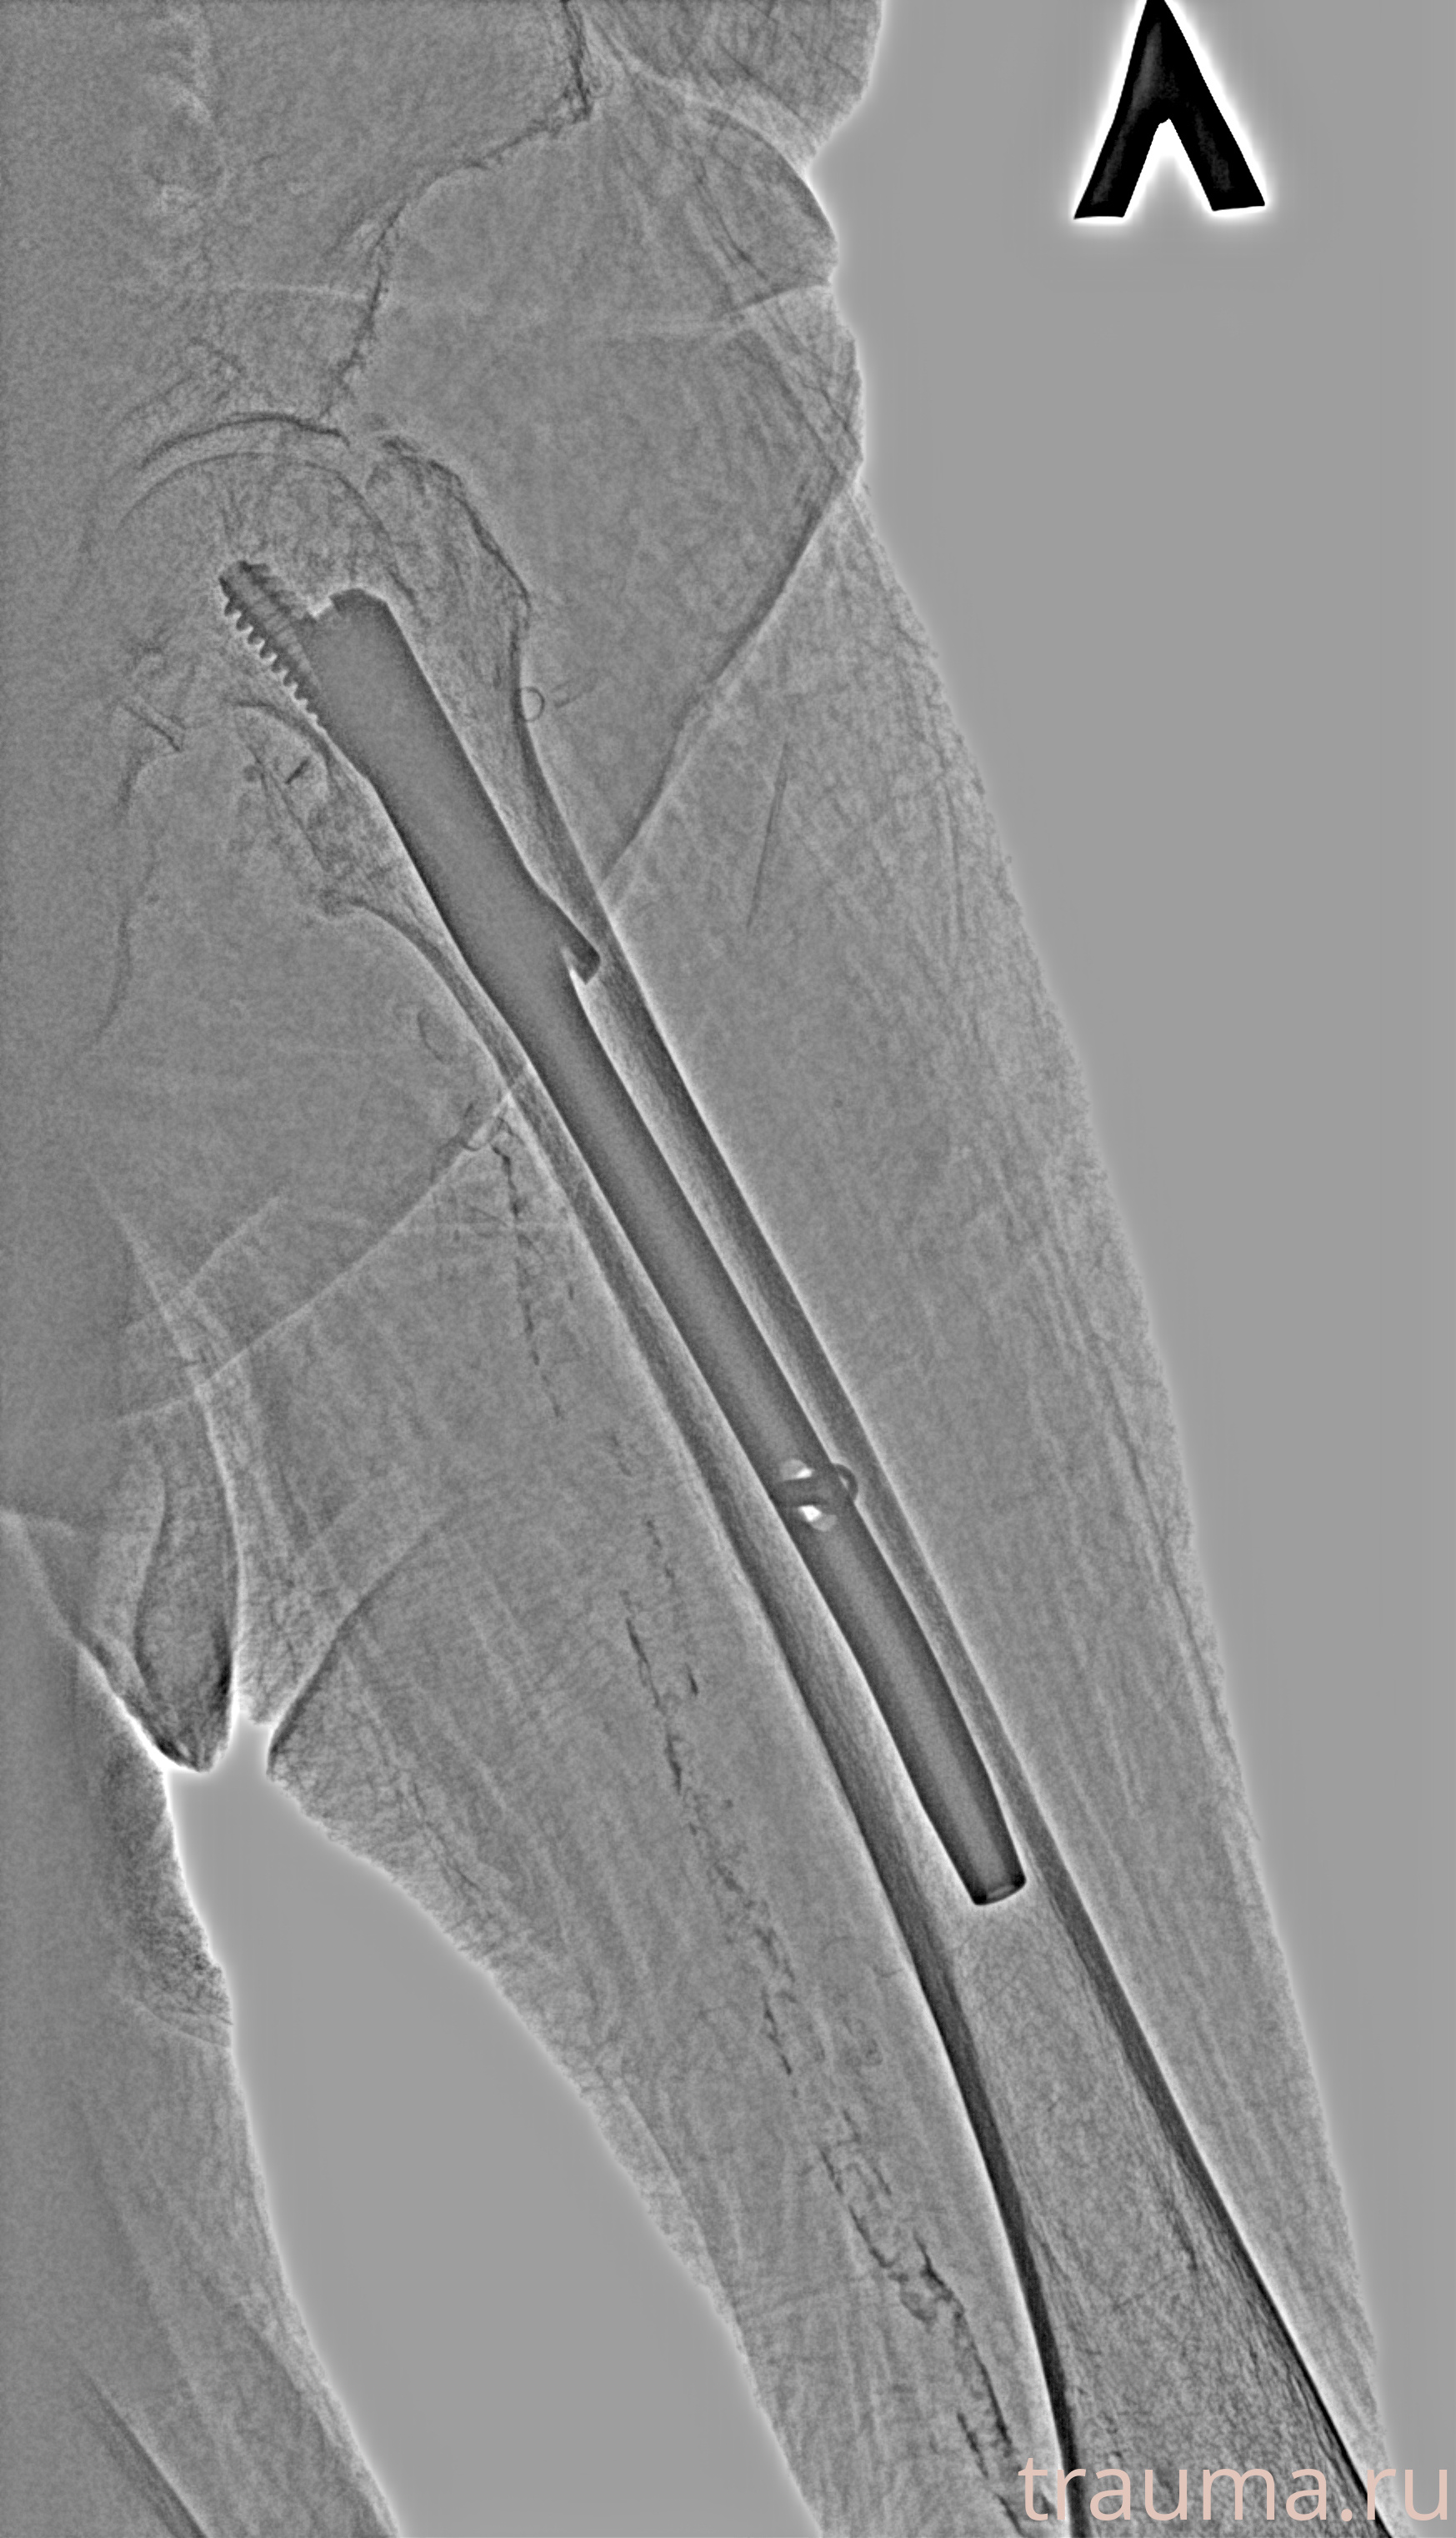

Рентгенограммы

Рентген на дому: по вашему адресу приезжает врач-рентгенолог, травматолог-ортопед с мобильным рентгеновским аппаратом, проводит диагностику травмы или заболевания, делает необходимые рентгенограммы, дает рекомендации по дальнейшему лечению. Получить качественные снимки в домашних условиях возможно благодаря уникальной методике, разработанной МосРентген Центром для института  Склифосовского